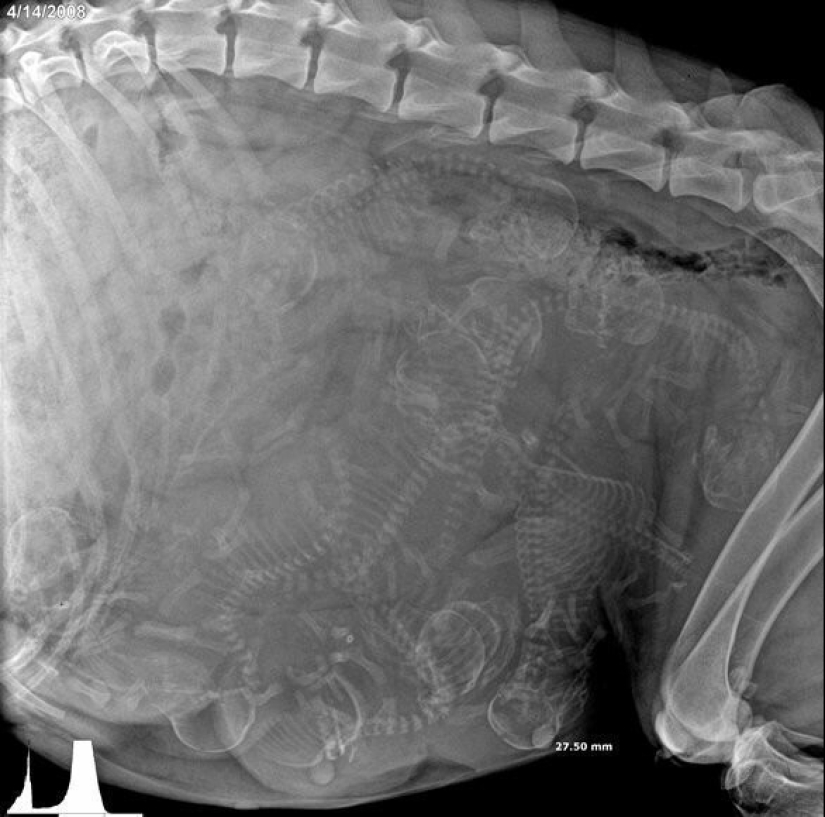

perra preñada